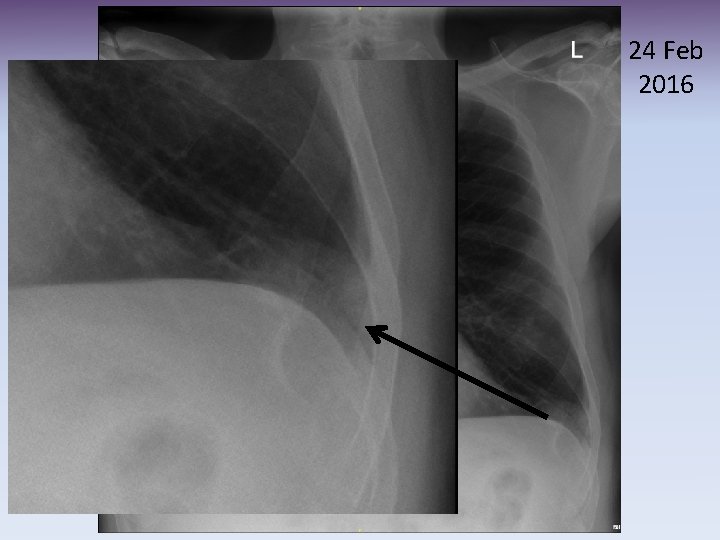

8 Dec 2015

24 Feb 2016